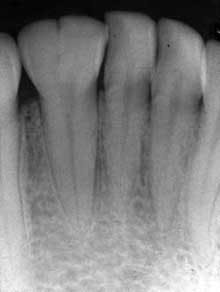

• Gemination — In gemination (see Figures 3, 4), a single-tooth germ tries to produces two teeth. The root system appears as one and then the tooth splits as the two crowns become visible. In other words, two crowns appear to arise from a single root. The maxillary incisors are most commonly affected. The incidence is dramatically decreased in the molar region, and a hereditary tendency is noted. The terms “twinning” and “double teeth” have been noted in the literature as well.

Figure 1: Clinical slide of tooth #18 with additional adjoining tooth in question. Photo courtesy of Kathryn Jendrasik-Savitsky, DDS. Figure 2: The radiograph vaguely supports two separate root canal systems. Also noted in the radiograph is a small focus of dense, radiopaque bone between the bicuspid and the first molar. This was diagnosed as “as a small zone of idiopathic osteosclerosis.” Photo courtesy of Jessica Huffman, RDH. Figures 3, 4: Gemination. Photos courtesy of Lippincott Williams & Wilkins from “General and Oral Pathology for the Dental Hygienist.” and Dr. Harvey Kessler. Figure 5: Fusion. Photo courtesy of Lippincott Williams & Wilkins from “General and Oral Pathology for the Dental Hygienist” and Dr. Harvey Kessler.